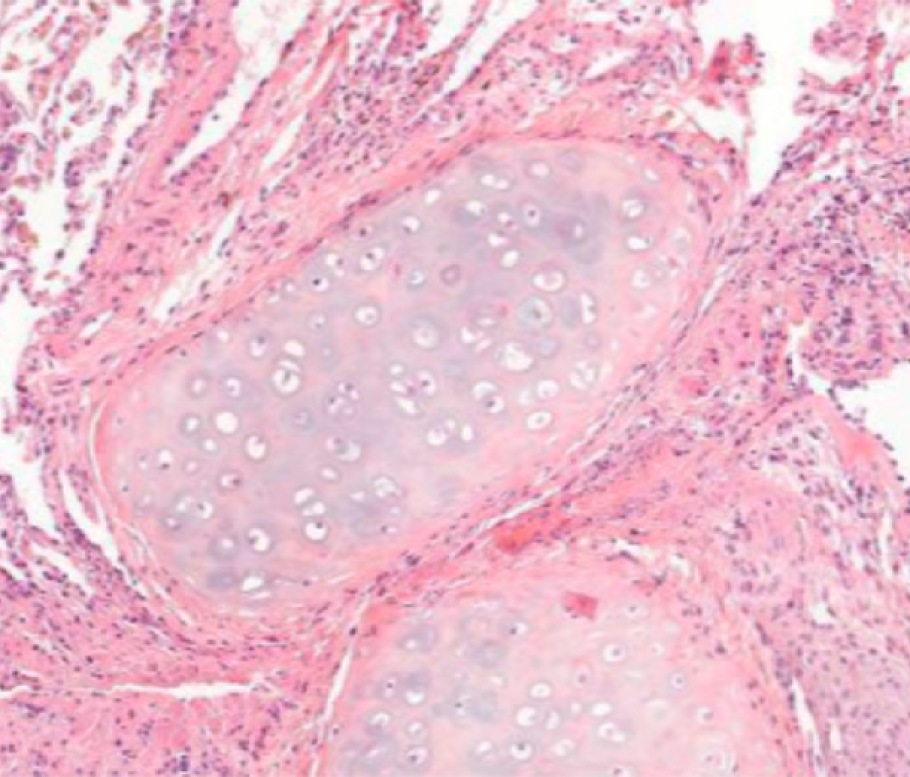

DigiLut : zoom sur la question médicale

La transplantation pulmonaire est le seul traitement curatif pour les maladies respiratoires terminales, avec environ 4 000 transplantations effectuées chaque année dans le monde. Malgré son potentiel vital, le succès de la transplantation reste étroitement liée au risque de rejet du greffon. Ce phénomène complexe et hétérogène est actuellement évalué par examen histologique, une méthode dont la reproductibilité demeure limitée.

Pour y remédier, l’hôpital Foch a lancé le challenge DigiLut dans le but d’assister grâce à l’IA les praticiens du monde entier dans la détection des épisodes de rejet de greffe dans le cadre des transplantations pulmonaires.

Une base de données unique de biopsies transbronchiques de patients greffés

L’hôpital Foch, principal centre de transplantation pulmonaire en France et l’un des meilleurs en Europe, a constitué une base de données inédite de plus de 2 500 lames numérisées d’anatomopathologie de biopsies transbronchiques de greffons pulmonaires, annotées par un panel international d’experts anatomopathologistes (États-Unis, Canada, France, Allemagne, Italie, Royaume-Uni, Pays-Bas) conformément à la grille LASHA “Lung allograft standardized histological analysis”.

Cette base de données a été mise à disposition sur la plateforme en ligne Trustii.io pour une durée de 2 mois, permettant ainsi à des équipes du monde entier de participer au challenge et de soumettre leurs modèles d’IA. Le but : créer un outil capable d'identifier des zones pathologiques dans les tissus pulmonaires de patients greffés.